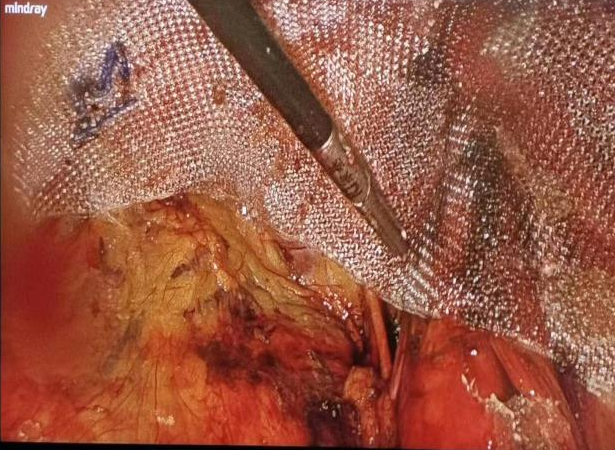

图2 TEP术式腹膜前间隙游离

图3 于腹膜前铺置3D补片